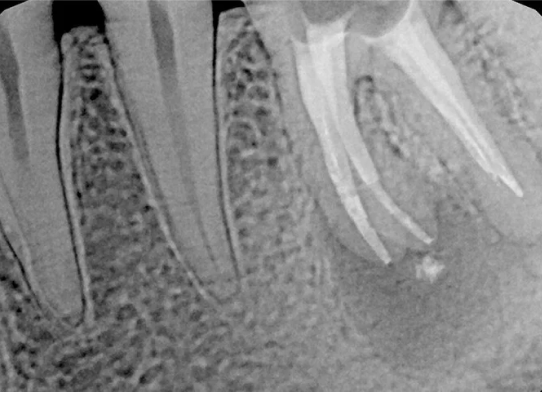

Po zakończonym leczeniu kanałowym, wykonujemy kontrolne zdjęcie RTG. Pozwala ono na natychmiastową ocenę jakości wypełnienia kanałów korzeniowych i potwierdzenie skuteczności przeprowadzonego zabiegu. Dla nas leczenie kanałowe Opole to synonim precyzji i pewności.

Na podstawie zdjęcia rentgenowskiego określa się kształt i długość kanału bądź za pomocą specjalnego urządzenia mierzy się jego długość. Potem lekarz otwiera wejścia do kanału, chroniąc ząb koferdamem, czyli specjalną gumą, zapewniającą sterylność oraz chroniącą przed środkami chemicznymi służącymi do oczyszcza-nia kanału. Używa się do tego zarówno specjalistycznego sprzętu, jak i nowo-czesnych mikroskopów, pozwalających na uzyskanie dokładnego obrazu leczone-go zęba. Ostatnią czynnością jest wypełnienie materiałem światłoutwardzal-nym i zabezpieczenie zęba przed dostaniem się i rozwojem bakterii mogących wywołać wtórny stan zapalny.

Przed rozpoczęciem leczenia kanałowego kluczowa jest dokładna diagnostyka. Zazwyczaj wykonujemy kontrolne zdjęcia RTG, a czasem nawet kilka, aby precyzyjnie ocenić stan zęba i otaczających go tkanek. W bardziej skomplikowanych przypadkach możemy zlecić wykonanie tomografii komputerowej (CBCT) dla uzyskania trójwymiarowego obrazu.

Nasza diagnostyka to nie tylko cyfrowe zdjęcia RVG (radiowizjografia), które ograniczają dawkę promieniowania i dają natychmiastowy obraz. W skomplikowanych przypadkach kierujemy pacjentów na tomografię komputerową CBCT, która daje trójwymiarowy obraz struktur zębowych i kostnych, co jest nieocenione przy planowaniu trudnego leczenia kanałowego lub ponownego leczenia endodontycznego.

W zależności od stopnia skomplikowania, leczenie kanałowe może być zakończone podczas jednej wizyty lub wymagać kilku spotkań. Zawsze dążymy do jak najszybszego, ale przede wszystkim jak najskuteczniejszego przeprowadzenia leczenia.